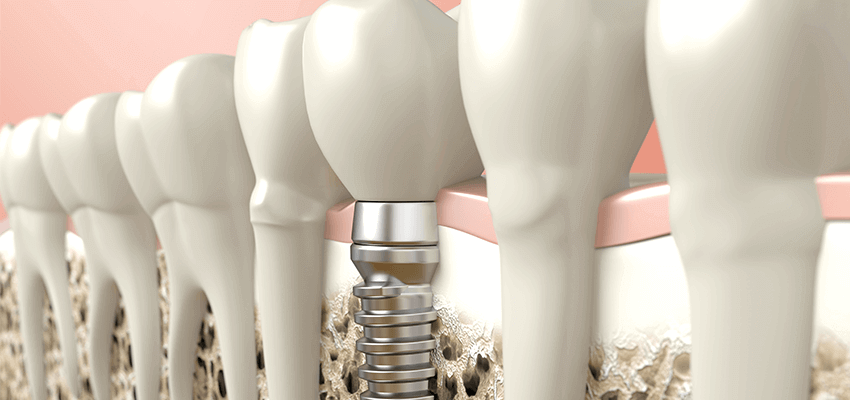

Nossa estrutura óssea está sempre em processo de formação e reabsorção, em um estado de equilíbrio dinâmico. Quando perdemos um dente, iniciam-se algumas alterações que resultam no desequilíbrio desse sistema, levando a reabsorção ou à atresia do osso alveolar.

A reabsorção óssea alveolar pode ser ocasionada por fatores como a perda precoce dos dentes, próteses removíveis, traumas, extrações dentárias e doenças periodontais. Isso interfere na reabilitação oral por meio de implantes, comprometendo assim o posicionamento correto dos dentes, a estética, a biomecânica e a funcionalidade dos dentes.

Muitos pacientes que tem indicação para a reabilitação com implantes deverão se submeter a algum procedimento reconstrutivo ósseo para sua correta instalação. Os enxertos podem ser realizados no momento da remoção do dente, antes da instalação dos implantes ou simultaneamente.